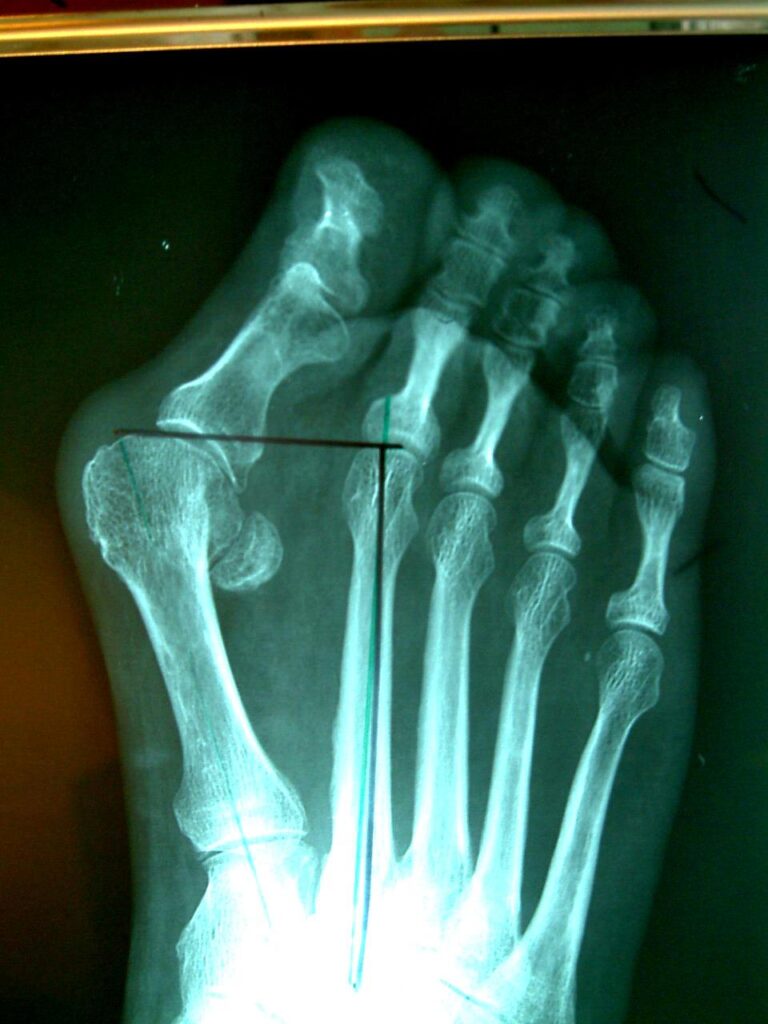

The common operative treatments of bunions involve bony correction through cuts of bone and fixation with screws as well as release of tight tissue structures and tightening of loose ones. Many operations for bunions have been tried over the years with varying levels of success. Techniques often vary from patient to patient depending or anatomy and bony alignment as well as soft tissue laxity.